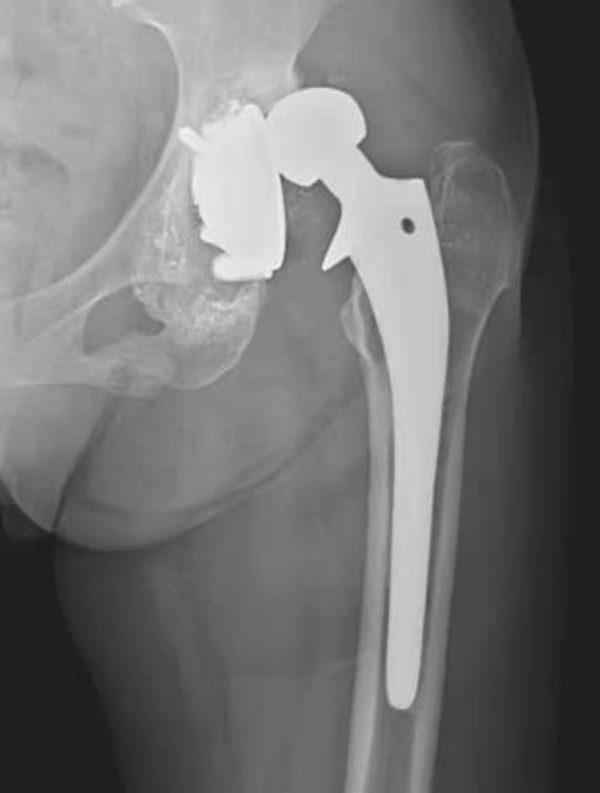

图4 右侧人工髋关节置换术后感染并松动

女性,89岁。发现右大腿中段后侧流脓2个月余。平片,示右股骨上段骨密度增高,内侧骨膜增生,假体周围骨质吸收,髋臼杯内陷,人工股骨柄部内移